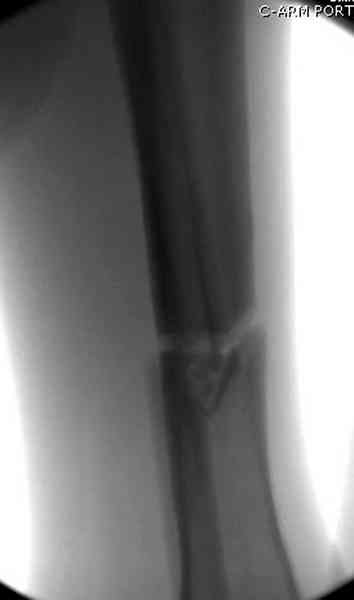

Больному с политравмой установлен наружный "spanning-bridging" фиксатор, после нескольких Irrigation&Debridment на фоне отрицательного посева из раны, через открытый участок установлен 4.5 mm Locking Plate.

На фоне фиксированного перелома бедра мероприятия по восстановлению мягкотканого покрова. Перелом голени зафиксирован после стабилизации бедра традиционным методом.

Антибиотические бусы могут быть оставлены в мягких тканях на длительный срок и не обязательно их удалять.

Из архива снимки самодельного "ваккумирования раны"